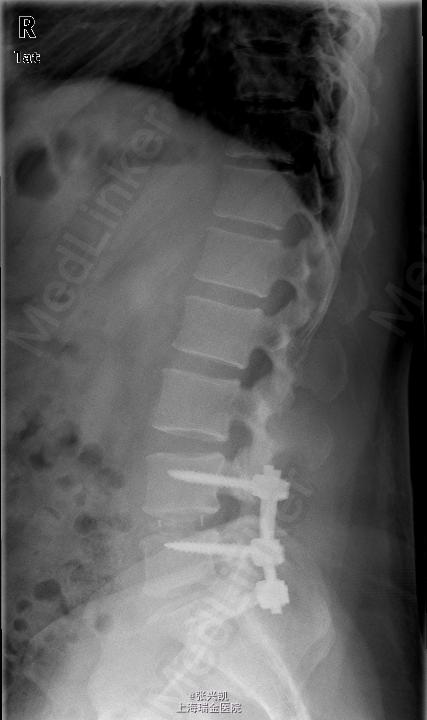

诊断: 1、腰椎椎间盘突出(L4-5,L5-S1) 2、腰椎椎管狭窄(L4-5,L5-S1) 处理: 经后路行L4-5,L5-S1椎管减压,椎间盘摘除,L4-5,L5-S1融合内固定术

随访:手术后一周即在医生指导下进行康复活动,卧床为主,一个月后解除腰围,进行基本生活劳动,3月后随访内固定器械位置良好,患者疼痛消失,一年后随访,患者椎体融合良好,双下肢感觉良好。 讨论:对于椎间盘突出压迫神经,时间较长,出现麻木等感觉的患者,应尽早手术解除压迫,有利于神经恢复,否则术后疼痛消失后,麻木的感觉可能一直存在,难以恢复。